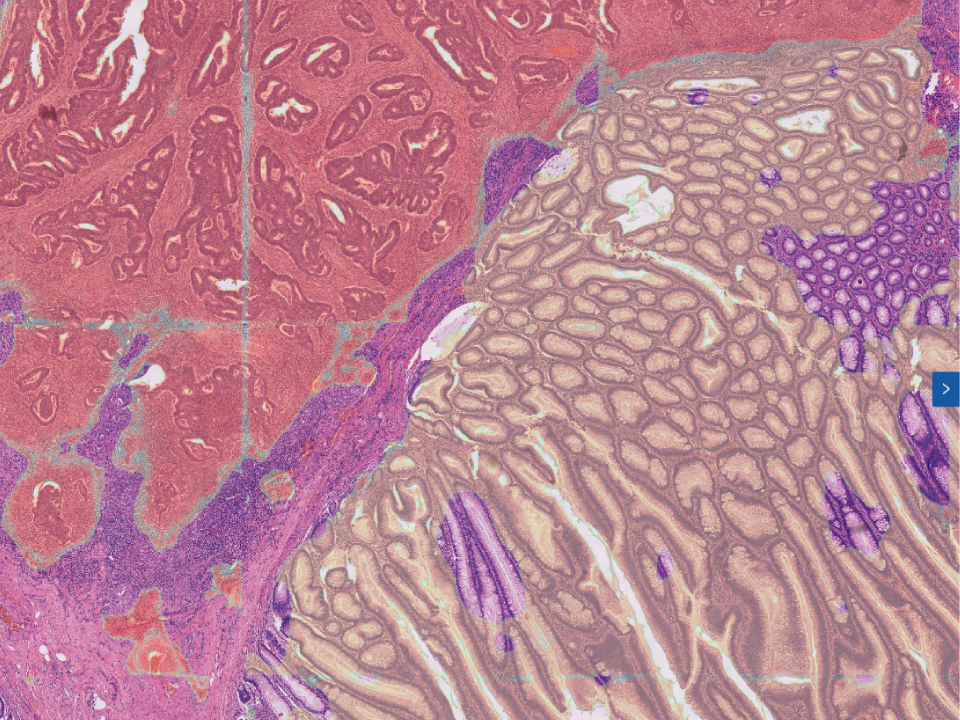

Gastric Biopsy Assistant Diagnostic Module

Efficient identification of tissue structural changes and cellular abnormalities. Automatically recognize eight lesion types,covering more than 95% of lesion types. Automatically capture the lesion area,effectively assist doctors in diagnosis. Combine pathology images, gastroscopy and medical history to improve physicians' diagnostic accuracy.

Gastric Biopsy Assistant Diagnostic Module

Efficient identification of tissue structural changes and cellular abnormalities.

Automatically recognize eight lesion types,covering more than 95% of lesion types.

Automatically capture the lesion area,effectively assist doctors in diagnosis.

Combine pathology images, gastroscopy and medical history to improve physicians’ diagnostic accuracy.